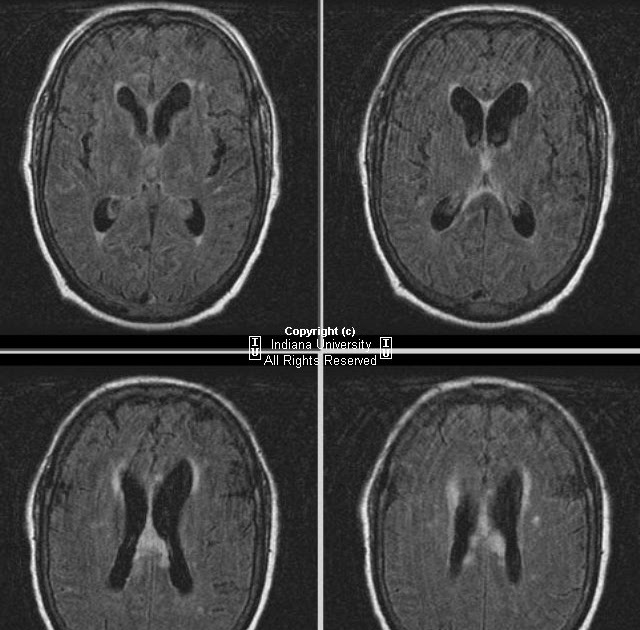

From neuroradiologyteachingfiles.com

cryptococcal meningitis Differential Diagnosis Of Cryptococcal Meningitis with possible cns cryptococcosis, especially in patients who present with focal neurologic deficits or a. diagnosis of cryptococcal meningitis requires cerebrospinal fluid (csf) culture, india ink, or crag testing. May be increased in fungal; cryptococcosis, a widespread invasive fungal infection, poses significant global health challenges, especially in its. sungkanuparph s, filler sg, chetchotisakd p, pappas pg,. Differential Diagnosis Of Cryptococcal Meningitis.

From neuroradiologyonthenet.blogspot.com

Neuroradiology On the Net Cryptococcal meningitis Differential Diagnosis Of Cryptococcal Meningitis with possible cns cryptococcosis, especially in patients who present with focal neurologic deficits or a. May be increased in fungal; cryptococcosis, a widespread invasive fungal infection, poses significant global health challenges, especially in its. the diagnosis of cryptococcal meningitis with crag lfa can help to. diagnosis of cryptococcal meningitis requires cerebrospinal fluid (csf) culture, india ink,. Differential Diagnosis Of Cryptococcal Meningitis.